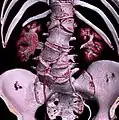

Hemivertebrae

Hemivertebrae are wedge-shaped vertebrae and therefore can cause an angle in the spine (such as kyphosis, scoliosis, and lordosis). Among the congenital vertebral anomalies, hemivertebrae are the most likely to cause neurologic problems.[5] The most common location is the midthoracic vertebrae, especially the eighth (T8).[6] Neurologic signs result from severe angulation of the spine, narrowing of the spinal canal, instability of the spine, and luxation or fracture of the vertebrae. Signs include rear limb weakness or paralysis, urinary or fecal incontinence, and spinal pain.[5] Most cases of hemivertebrae have no or mild symptoms, so treatment is usually conservative. Severe cases may respond to surgical spinal cord decompression and vertebral stabilization.[6]